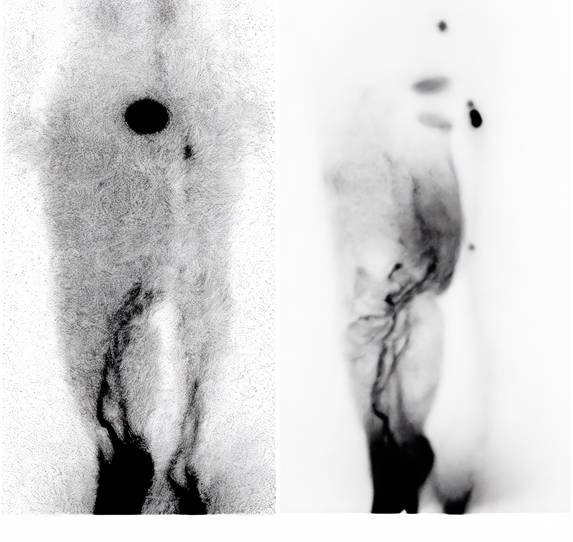

Seven patients underwent lymphoscintigraphy at 12 months. All demonstrated findings suggestive of functional improvement, including increased tracer uptake in the transferred omental flap (Figure 5), clearer visualisation of lymphatic trunks, reduced dermal backflow, and fewer collateral channels (Figure 6). Comparative analysis was not feasible in five patients due to flap failure (n = 1), loss to follow-up (n = 1), or incompatible preoperative imaging protocols (n = 3).

Figure 6

(A) Preoperative lymphoscintigraphy showing dermal backflow throughout the right leg, with main lymphatic vessels visible only below knee level. (B) Lymphoscintigraphy one year postoperatively showing significant improvement in lymphatic drainage. Main lymphatic vessels were visible above knee level, with reduced dermal backflow.

These findings are consistent with previous reports by Ciudad et al.[12] and Nguyen et al. [18, 22], who demonstrated clinical and functional improvement following laparoscopic omental VLNT. Our results are further corroborated by recent extensive clinical experiences reported by Pozzi et al., which reaffirmed that gastroepiploic VLNT is a highly effective and safe procedure for extremity lymphedema, offering significant improvements in limb circumference and tissue tonicity with minimal donor-site morbidity [26]. Notably, our lymphoscintigraphy suggested not only improved drainage but also radiotracer uptake within the transferred flap, supporting the concept of neo-lymph node formation through lymphangiogenesis and functional integration into the host lymphatic network. This aligns with prior experimental studies showing that transplanted lymph nodes secrete VEGF-C and VEGF-D, which stimulate VEGFR-3-mediated lymphangiogenesis and promote the regeneration of lymphatic sinuses and high endothelial venules (HEVs) [12, 18, 22].

The observed greater reduction in distal limb circumference further supports the biological mechanism: placing the omental flap at the ankle optimises gravitational drainage and provides a local microenvironment for lymphangiogenesis. The improved uptake and reduced dermal backflow on lymphoscintigraphy are consistent with the establishment of new lymphatic pathways and the functional maturation of neo-lymph nodes.